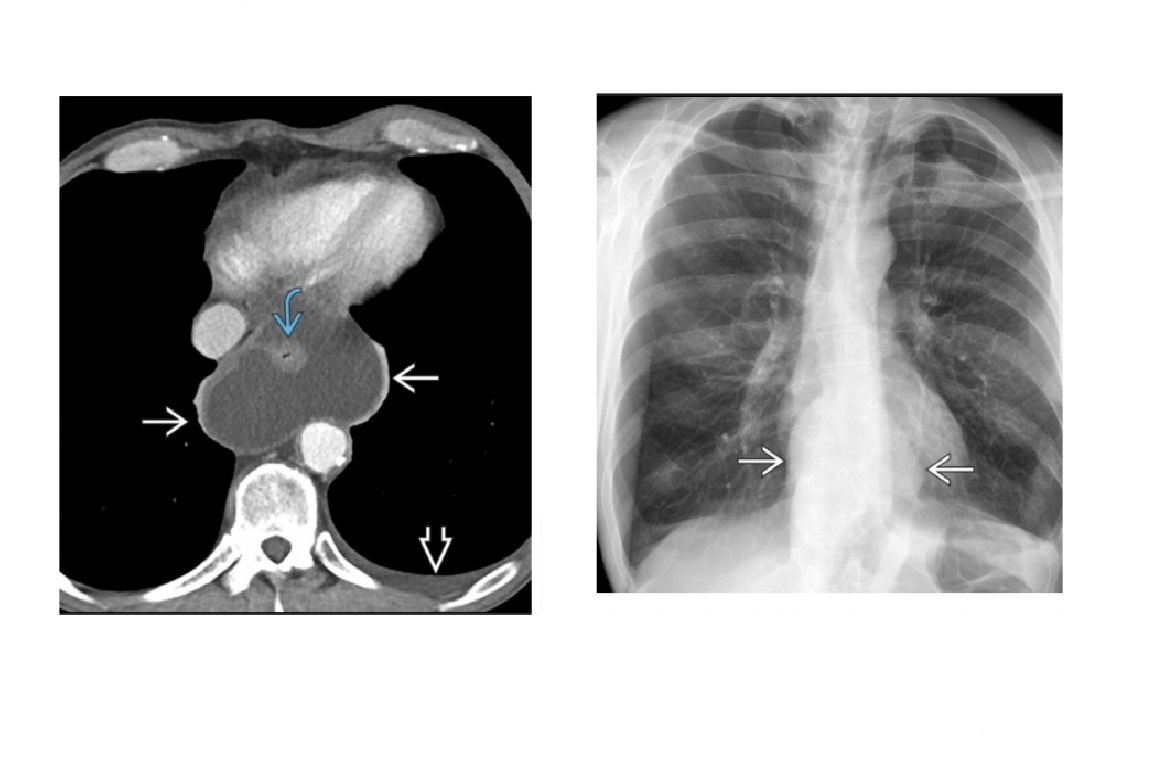

Pulmonary sling

Aberrant left pulmonary artery

Anterior indentation of the oesophagus and posterior indentation of the trachea